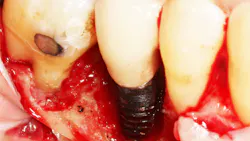

Recent studies suggest a role of SSRI intake and reduced bone mineral density, with an increase in bone fracture.4 The effect of SSRI use on implant success rates is not clear, but one study evaluated 94 implants placed over five years and saw a double in implant failure rates when comparing patients taking SSRIs and those not taking the medication.5 Another more recent study evaluated 2,055 implants placed over a two-year period. This study suggested a threefold increase in the number of failures in patients taking SSRIs compared to those who did not take the medication.6 When unexplained bone loss occurs around an implant and the patient has been on a long-standing SSRI medication, consideration should be given to this possible etiology (figure 1).

The effect PPIs have on implants is not clear, but one study looked at 3,560 implants placed in 1,000 patients over a 35-year period. Results found a 12% failure rate in PPI users versus nonusers.8 Another study evaluated 1,773 implants placed in 800 patients and found the failure rate doubled when comparing PPI users and nonusers.9 When unexplained bone loss occurs around an implant and the patient has been on long-standing PPI medication, consideration should be given to this possible etiology (figure 2).